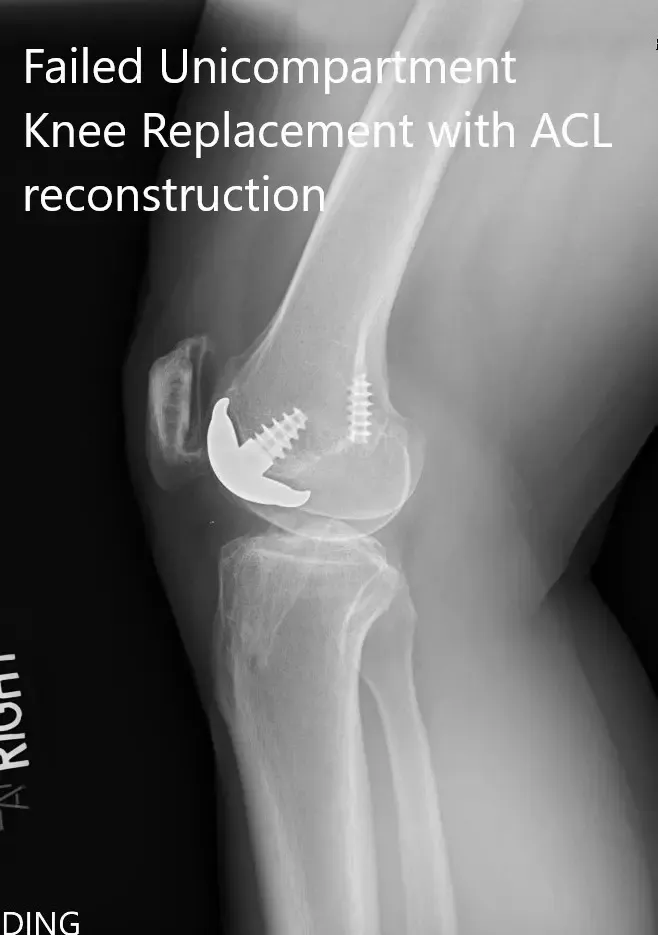

Preoperative x-ray showing the anteroposterior and lateral views of the right knee

PREOPERATIVE DIAGNOSIS(ES): Failed Right knee unicondylar knee replacement.